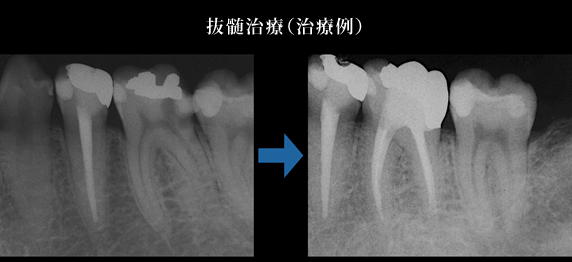

5.経過観察後の治癒の確認

治療後の症状の変化をレントゲンで確認します。